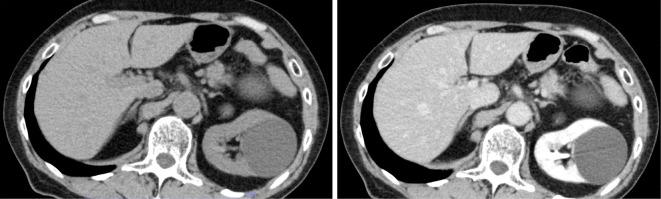

Fat-stranding Sign: A Clue of Visceral Disseminated Varicella-zoster Virus Infection.

Fat-stranding Sign: A Clue of Visceral Disseminated Varicella-zoster Virus Infection.脂肪浸润征:内脏播散性水痘-带状疱疹病毒感染的一个线索

Periarterial Fat Stranding as a Diagnostic Marker for Visceral Disseminated Varicella-Zoster Virus Infection.动脉周围脂肪条索征作为内脏播散性水痘-带状疱疹病毒感染的诊断标志物

Disseminated Varicella zoster infection with abdominal pain and periarterial fat stranding in a patient taking pomalidomide.一名服用泊马度胺的患者发生播散性水痘带状疱疹感染并伴有腹痛和动脉周围脂肪条索征。